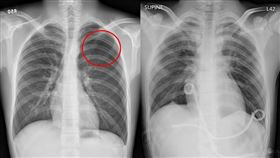

女手痛、胸腔藏成熟畸胎瘤:有頭髮、牙齒

28歲的張小姐前陣子因為左手痛,陸續到診所看中醫與復...

高瘦男性胸痛別輕忽!當心自發性氣胸

過去曾有氣胸病史的15歲鄭同學,日前因左胸劇烈疼痛,...